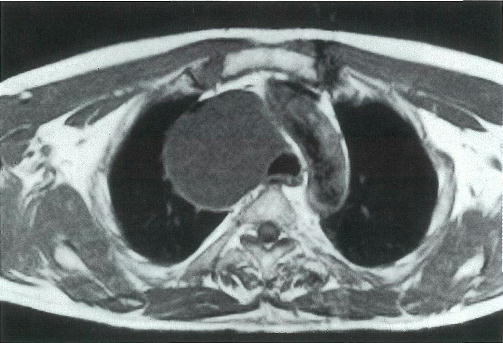

43歳の男性。健康診断の胸部エックス線写真で腫瘤陰影を指摘されて来院した。胸部単純MRIのT1強調像とT2強調像とを別に示す。

腫瘤の性状として最も考えられるのはどれか。

a 気体

b 漿液

c 線維

d 脂肪

e 石灰

× a

○ b

× c

× d

× e

正解 b

診断 縦隔嚢胞(胸腺嚢胞など)